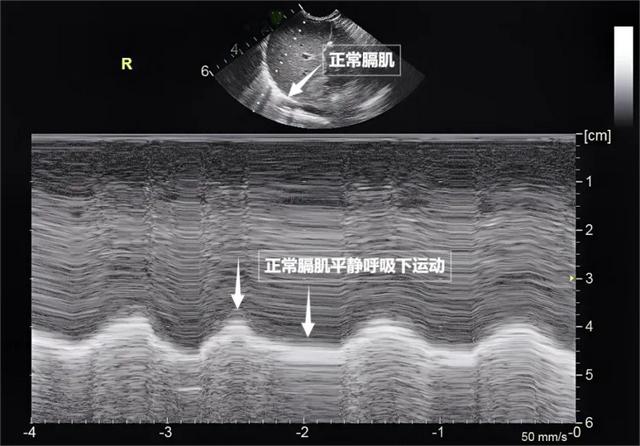

图为正常新生儿肺部超声表现第三景:“呼吸的动力泵”的协同作战——呼吸肌肉呼吸看似简单,实则是多组肌肉精密配合的“团体操”。肺部超声不仅能观察肺的形态,更能通过实时动态影像,“捕捉”这些呼吸肌的活动状态,为评估呼吸功能提供独特视角。膈肌是呼吸肌的“总指挥”,位于胸腔与腹腔之间。平静呼吸时,膈肌收缩下沉,胸腔容积扩大,空气自然吸入;舒张时,膈肌回升,肺部弹性回缩完成呼气。超声下可见膈肌呈光滑弧形,随呼吸规律上下移动(见下图)。肋间外肌则是“肋间隙的升降机”,收缩时上提肋骨,扩大胸腔前后径,辅助吸气。这对“黄金搭档”承担了日常呼吸70%以上的工作量,是维持呼吸的“主力军”。

图为正常膈肌超声表现当身体需要更多氧气时(如上楼梯),斜角肌和胸锁乳突肌便会“增援”。在极端情况(如哮喘发作)下,腹壁肌群和肋间内肌会紧急出动。肺部超声这位“侦察兵”,通过观察肌肉激活顺序、测量膈肌厚度与移动度、捕捉肌肉矛盾运动,动态评估呼吸肌肉的变化,早期发现呼吸系统“超负荷运转”的信号,为医生调整治疗方案提供精准依据。